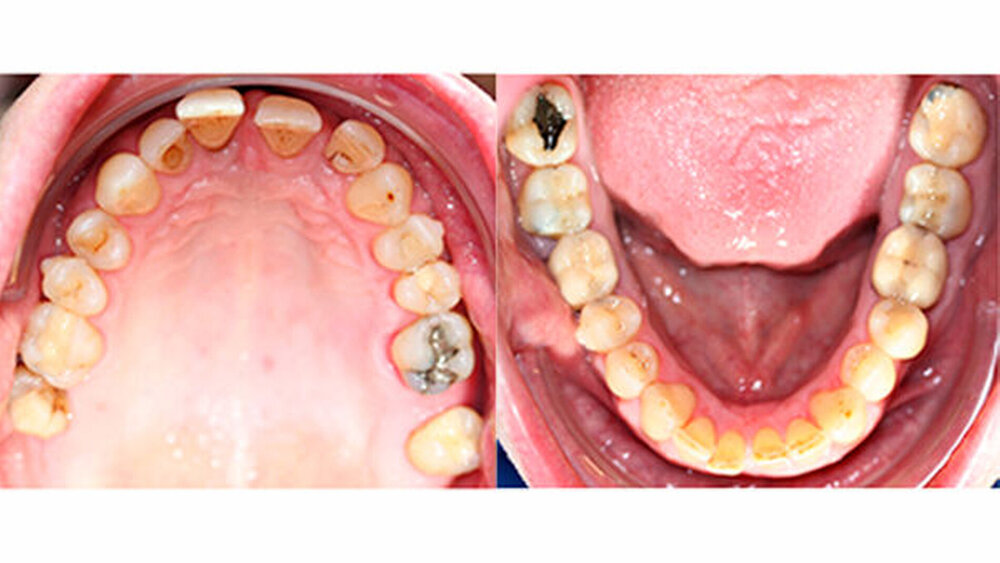

Intraoral zeigte sich ein bereits konservierend versorgtes permanentes Gebiss mit aktivem und inaktivem kariösen Geschehen. Große Anteile der Zahnhälse lagen nach Zahnfleischrückgang in Kombination mit Knocheneinbrüchen frei. Zahn 27 wurde bereits extrahiert.

Eine Beurteilung der parodontalen Situation an Zahn 11 offenbarte mesial und distal Sondierungstiefen von jeweils 6 mm.

Kieferorthopädisch imponierte beidseits eine neutrale Verzahnung bei einem tiefen Biss von 5 mm - bedingt durch die Verlängerung beider Frontzahngruppen. Besonders Zahn 11 zeigte eine erhebliche Verlängerung und Protrusion mit einer sagittalen Frontzahnstufe von 5 mm. Sowohl die Frontzähne im Ober- als auch im Unterkiefer wiesen eine lückige Beziehung zueinander auf (Abbildung 1).